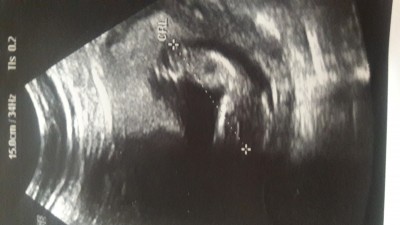

Mrb  cinsiyet tahmini yapabilen anneler yardımcı olurmusuniz

Gebelik haftası 12+6

Pek  belli  olmuyor  20 haftada  anca